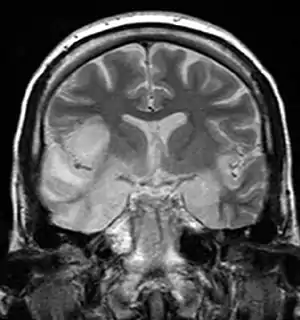

大多數患有單純皰疹腦炎的人會因意識水平下降和精神狀態改變而出現混亂和人格改變。患者腦脊液中白細胞數量會增加,但不存在病原菌和真菌。患者通常會發燒[1],並可能出現癲癇發作。隨著疾病的進展,大腦部活動會發生變化,首先顯示大腦一個顳葉異常,7-10天後會擴散到另一個顳葉。[1] CT或MRI成像顯示顳葉的特徵性變化(見圖)。